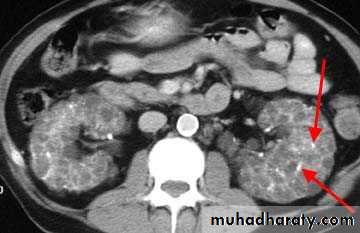

CT also shows enlarged kidneys with multiple cysts appears as low attinuated areas

Poly cystic kidney